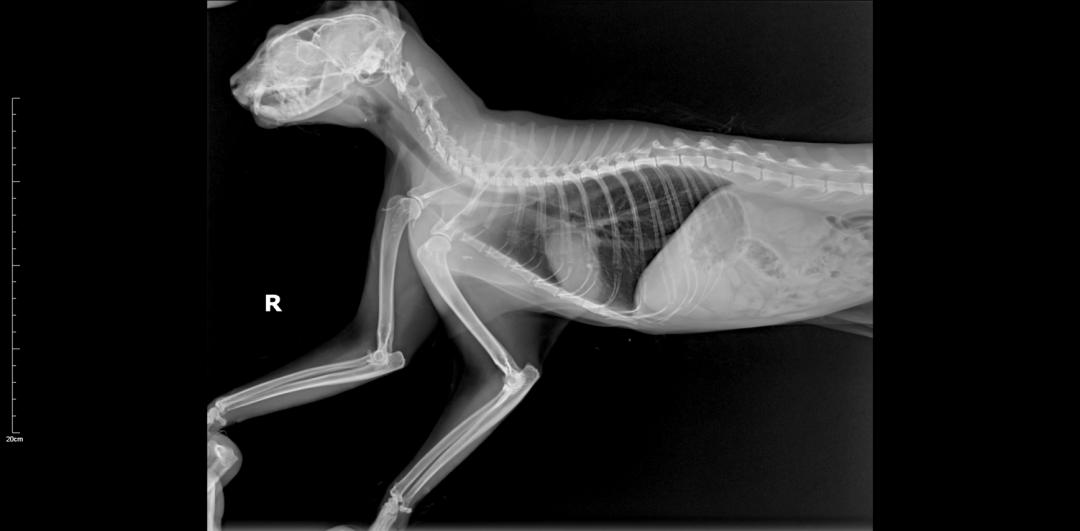

DR↓↓

胸腰椎、四肢未见明显骨折;面部、鼻腔、多处骨折。